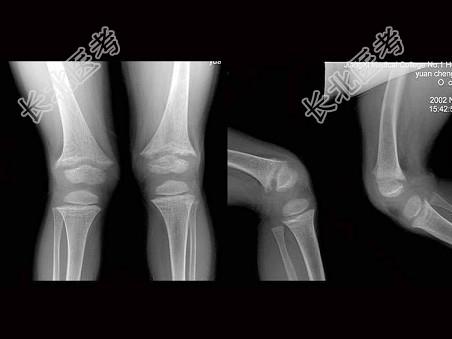

单项选择题男,6岁, 身材矮小,关节畸形, 血钙磷化验异常,如图, 最可能的诊断为 ( )

A、坏血病

B、肾性佝偻病

C、粘多糖病

D、克汀病

E、脂质沉积病